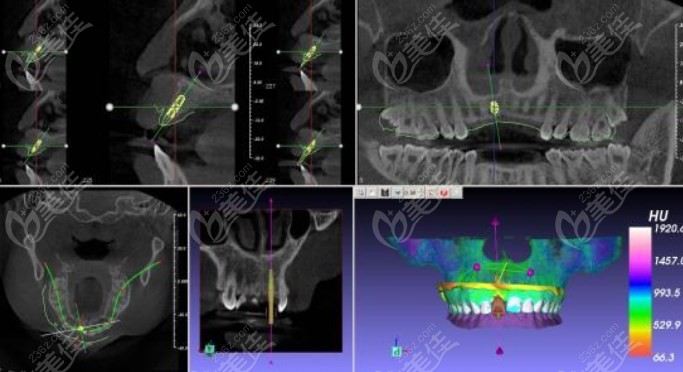

①3D数字化种植术——在数字化种植导板下导航种植,可详尽位种植体的角度与深度。